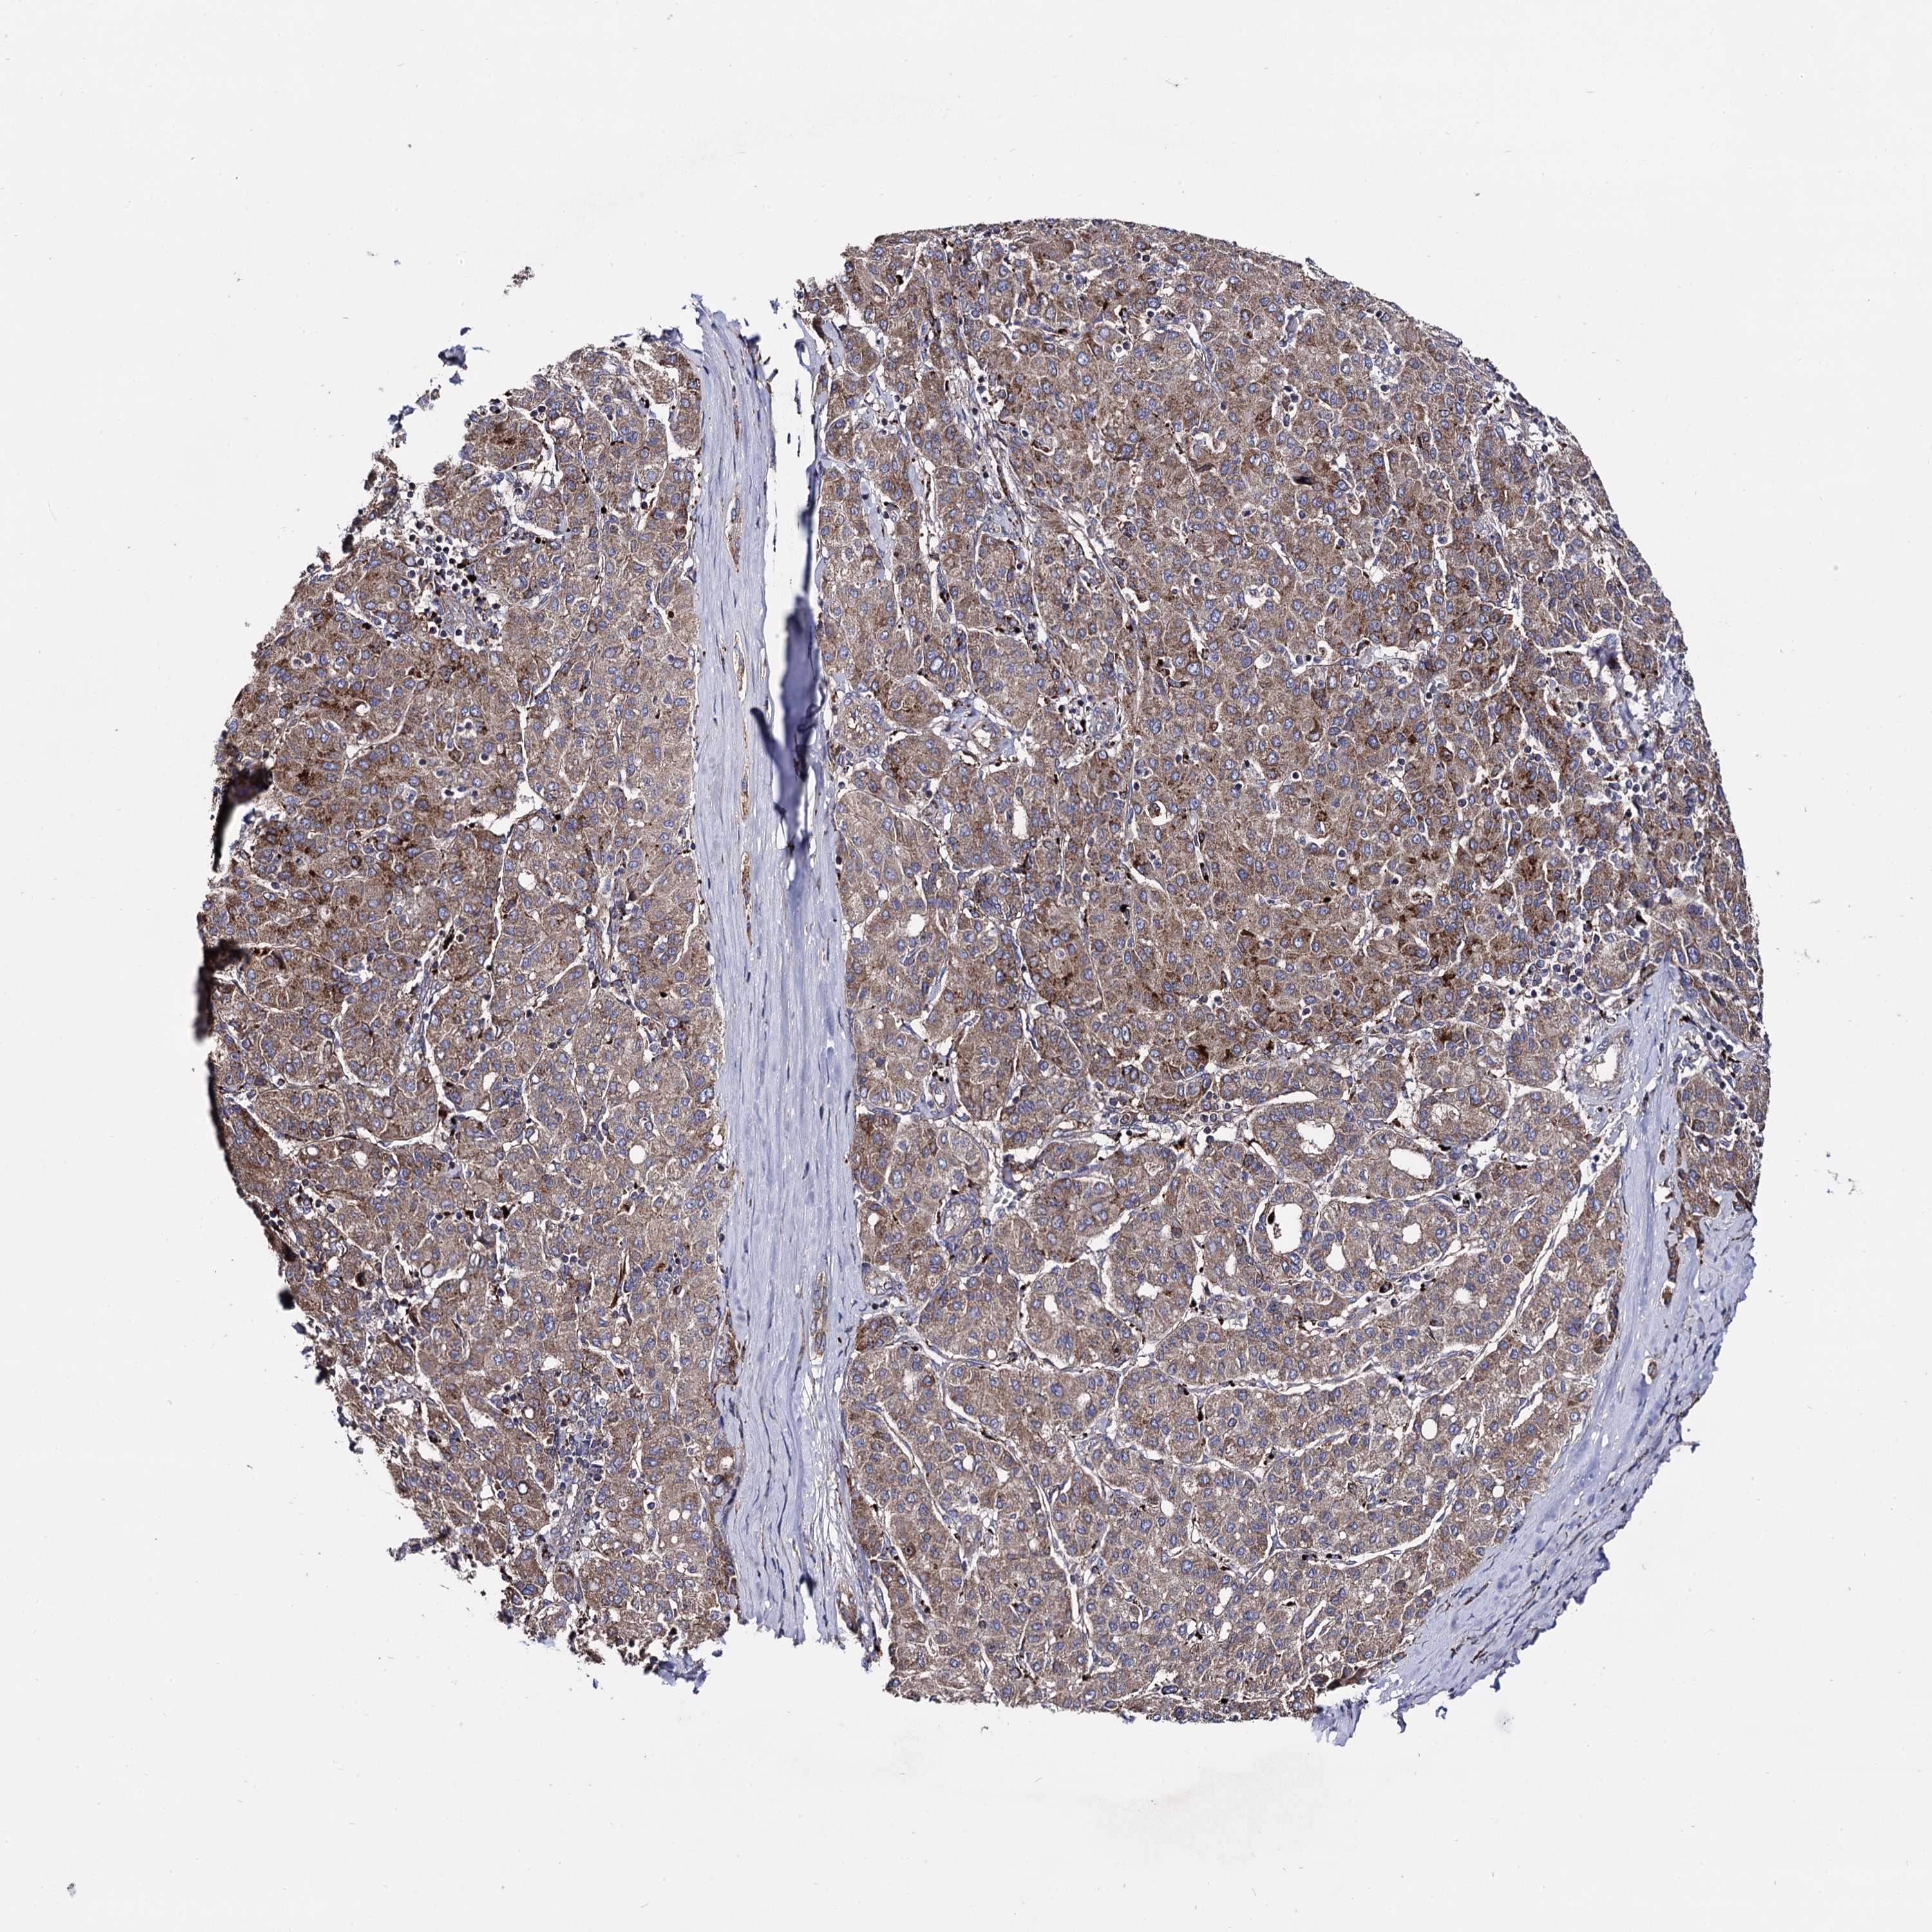

LIVER CANCER - Protein expressioni

A mouse-over function shows sample information and annotation data. Click on an image to view it in a full screen mode. Samples can be filtered based on level of antibody staining by selecting one or several of the following categories: high, medium, low and not detected. The assay and annotation is described here.

Note that samples used for immunohistochemistry by the Human Protein Atlas do not correspond to samples in the TCGA dataset.

Antibody stainingi

Antibody staining in the annotated cell types in the current human tissue is reported as not detected, low, medium, or high, based on conventional immunohistochemistry profiling in selected tissues. This score is based on the combination of the staining intensity and fraction of stained cells.

Each image is clickable and will lead to virtual microscopy that enables deeper exploration of all samples and also displays staining intensity scores, fraction scores and subcellular localization as well as patient and tissue information for each sample.

Antibody HPA040845

Staining

High

Medium

Low

Not detected

Intensity

Strong

Moderate

Weak

Negative

Quantity

>75%

75%-25%

<25%

None

Location

Nuclear

Cytoplasmic/membranous

Cytoplasmic/membranous,nuclear

Cholangiocarcinoma

Carcinoma, Hepatocellular, NOS